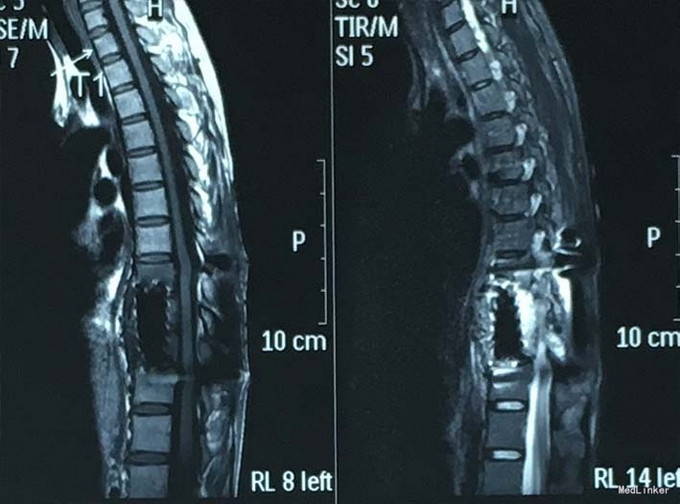

查体:脊柱外观无明显畸形,颈椎活动度正常,胸背部可见纵向长约15cm切口,皮肤钉缝合,伤口愈合可,无红肿渗液。胸椎9-10体左侧棘突旁局部压痛(+)、叩击痛(-),压头试验阴性,双侧侧臂丛牵拉实验(-),双上肢肌张力、运动、感觉及反射无明显异常、躯体感觉无明显减退,双下肢髂腰肌、股四头肌、胫前肌肌力IV级,感觉正常,双下肢直腿抬高试验(-),双侧腱反射对称略活跃,双侧Hoffman征(-),双侧Babinski征(-),双侧髌阵挛(-),踝阵挛(-)。 辅助检查:2015-11外院胸椎MRI检查发现T9-10节段椎体肿瘤并椎旁软组织肿块形成,肿块突入胸腔占位

诊断:胸椎椎体肿瘤(T9-10) 治疗:先于外院行1期后路椎弓根钉固定融合手术,然后转入我院行介入下术前椎体节段血管栓塞手术,第二天行经左侧胸腔入路椎体肿瘤病灶刮除并钛网植骨植入重建手术。术后恢复满意。复查MRI显示肿瘤病灶基本完全切除。